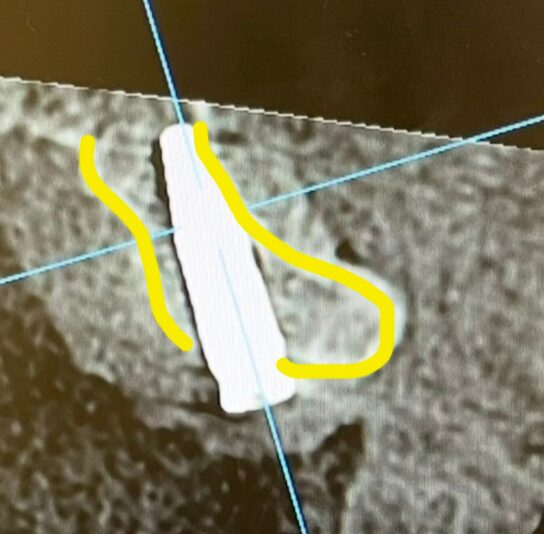

Good day everyone ! Recently I have placed an implant in the 23 region without using a guide. Patient has a prominent buccal exostosis and low smile line. However the bone apical to the bony exostosis is narrow. I made a mistake by focusing too much on getting the ideal screw channel axis and placed the implant too lingually.

While the cervical half of the fixture is well surrounded by thick labial bone but the apical half has nearly perforated the labial bone.

In this case, asethetic may not be a significant but in terms of the success rate of implant, but does thin or absent labial bone around the apical half could negatively impact the implant’s success rate?

This is a very common issue and it is great that you did not actually break through the labial plate. Although it looks very thin on the CBCT in that region, if you flapped it you might find that there is still bone covering the implant and that no exposure is present. (I am not advising you to flap it!)

I have actually seen a few studies about this, where the CBCT shows no to little bone but the implant is successful even after a decade. The main factor in these cases was the about of soft tissue. It being so apically I would not worry about it, learn from it and keep going. I see no reason why it would impact the success of the case. Like Ivan said, the buccal plate doesn’t seem to be perfed so you should be fine.